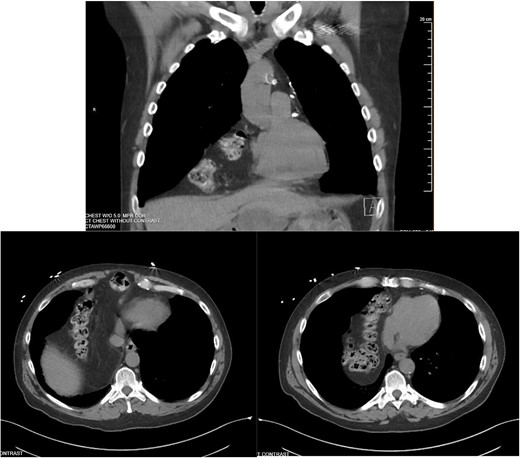

He was admitted for nasogastric decompression and underwent an upper endoscopy with benign findings. Once stable, he was discharged and optimized as an outpatient by adhering to a high-protein liquid diet. He underwent a scheduled robotic-assisted transabdominal preperitoneal (r-TAPP) repair of a type 4 anterior diaphragmatic hernia with mesh. The robot was docked and targeted with four 8 mm robotic ports across the mid-abdomen. A moderately sized hernia containing a loop of the transverse colon was identified. This was gently reduced (Fig. 3).